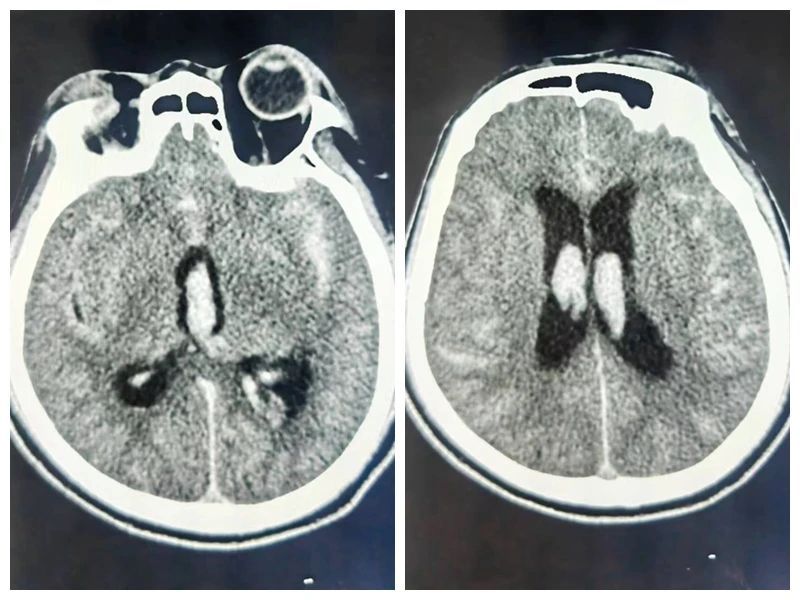

患者头颅CT可见广泛的蛛网膜下腔出血及脑室积血

在没有头部外伤史的情况下,自发性蛛网膜下腔出血中50-80%是颅内动脉瘤这个颅内“炸弹”破裂造成的。入院后王振华主治医师立即给病人做了脑DSA检查。

在刘展会主任“一站式”破裂动脉瘤治疗理念的指导下,术后立即为患者行脑室外引流,尽快将脑室积血、蛛网膜下腔出血引流出来。术后病人很快恢复了意识,一周后脑室积血及蛛网膜下腔出血基本清除,继续康复治疗。